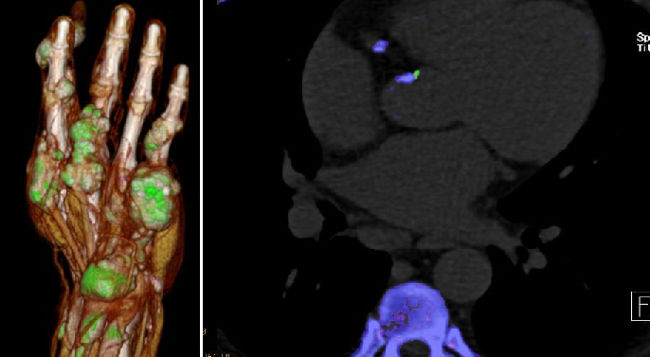

Musculoskeletal Imaging

Andrea S. Klauser et al., Multicentre collaboration for indication in MSK imaging and interventions

- Dual-energy CT (DECT) in gout: comparison with US, findings in extra-articular regions and cardio in gout and subgroup patients

- X-ray in comparison with DECT in gout patients

- Klauser AS, Halpern EJ, Strobl S, Gruber J, Feuchtner G, Bellmann-Weiler R, Weiss G, Stofferin H, Jaschke W.: Dual-Energy Computed Tomography Detection of Cardiovascular Monosodium Urate Deposits in Patients With Gout. JAMA Cardiol. 2019 Oct 1;4(10):1019-1028.

- Strobl S, Kremser C, Taljanovic M, Gruber J, Stofferin H, Bellmann-Weiler R, Klauser AS.: Impact of Dual-Energy CT Postprocessing Protocol for the Detection of Gouty Arthritis and Quantification of Tophi in Patients Presenting With Podagra: Comparison With Ultrasound. AJR Am J Roentgenol. 2019 Dec;213(6):1315-1323.